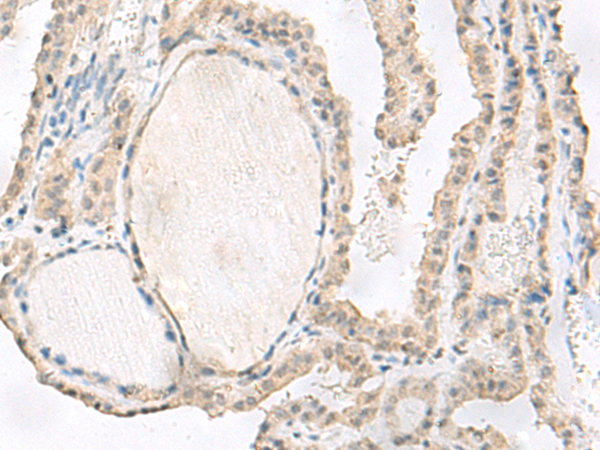

分类: 科研抗体货号: P06455别名: IL28A; IL-28A应用: IHC反应种属: Human